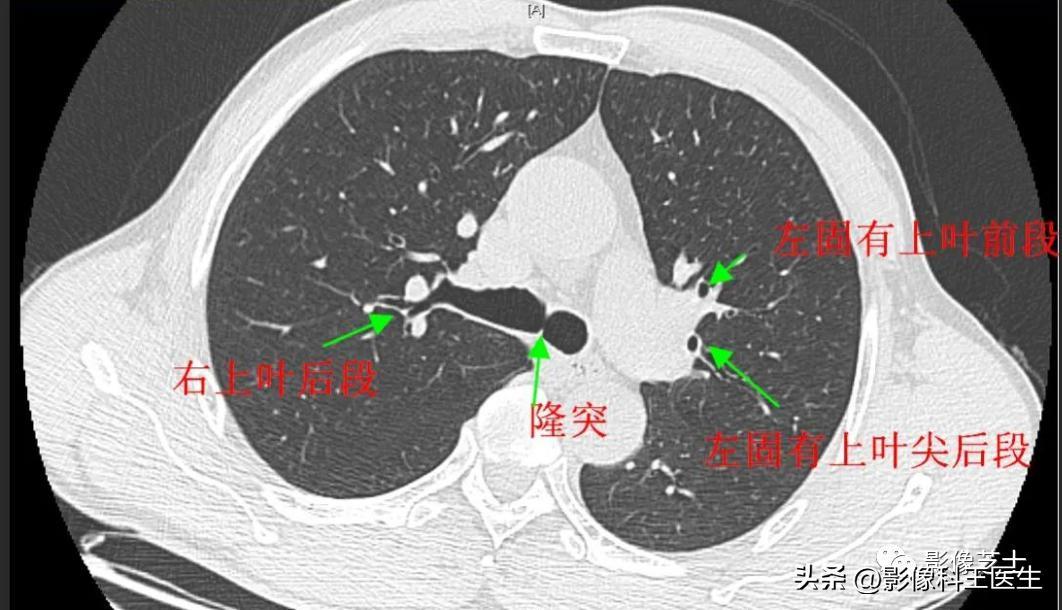

肺段、支气管分段CT解剖(详细标注)

肺部解剖分叶分段CT

上叶支气管

尖段支气管 前段支气管 后段支气管

中间支气管

肺的分段